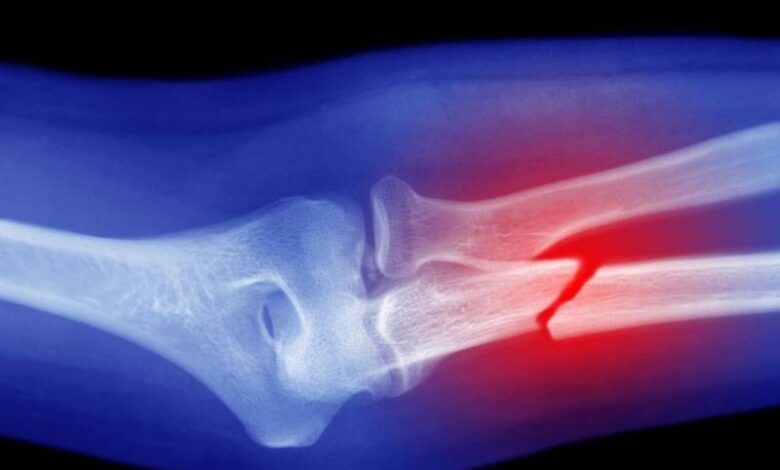

به گزارش سیناپرس، دانشگاه کینگز کالج لندن در پژوهش جدیدی نشان داده است پشم میتواند جایگزین مؤثر و پایداری برای موادی باشد که در حال حاضر برای ترمیم استخوانهای آسیبدیده استفاده میشوند.

پژوهش جدید دانشمندان «کینگز کالج لندن»(King’s College London) نشان میدهد کراتین که یک پروتئین طبیعی بهدستآمده از پشم است، از بازسازی استخوان حیوان زنده پشتیبانی میکند و به تولید بافت استخوانی میپردازد که نسبت به استاندارد طلایی کنونی، شباهت بیشتری به استخوان طبیعی و سالم دارد.

دانشمندان در مرحله بعد، غشاها را روی موشهایی آزمایش کردند که نقصهای جمجمه آنها بسیار بزرگ بود؛ در حدی که به طور طبیعی بهبود نمییافت. دانشمندان طی چند هفته، نحوه حمایت غشاهای کراتین از رشد استخوان جدید را در مناطق آسیبدیده بررسی کردند.

به نقل از ایسنا، اگرچه غشاهای کلاژنی در مجموع استخوان بیشتری تولید کردند، اما داربستهای کراتینی، استخوانی را به وجود آوردند که سازمانیافتهتر و از نظر ساختاری ایمنتر بود و الیاف آن با هماهنگی بهتری قرار داشتند که شباهت زیادی به استخوان طبیعی و سالم داشت. همچنین، غشاها به نرمی با بافت اطراف ادغام شدند و در طول فرآیند بهبود پایدار ماندند که هر دو ویژگی برای استفاده پزشکی در دنیای واقعی ضروری هستند.